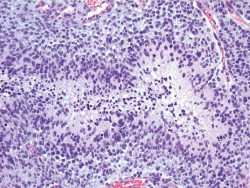

Estudio revela la primera evidencia de que la genética heredada puede favorecer la propagación del cáncer

A veces el cáncer permanece estático donde aparece pero a menudo se metastatiza, extendiéndose a otras partes el cuerpo. Desde hace tiempo se sospecha que las mutaciones genéticas que surgen dentro de las células tumorales impulsan este giro de eventos potencialmente devastador. Ahora los investigadores han demostrado por primera vez que nuestra propia genética puede promover la metástasis.